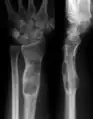

X-ray image showing enchondromas localized in the lower part of the radius of a 7-year-old girl with Ollier disease.

Abnormal bone growth such as shortening or thickening and deformity may be observed in patients of Ollier disease. These bone lesions are visible at birth using radiography but are usually not screened or examined for until clinical manifestations present during early childhood. However, some patients may exhibit no signs of any symptoms.[1] One study found thirteen to be the mean age of diagnosis in patients with Ollier disease. In an X-ray, there would normally be the presence of several homogeneous lesions of an oval or elongated shape with bone edges that are slightly thickened.[3] With age, these lesions may calcify and appear as diffusely minute spots or stippled. Fan-like septations or streaks would be indicative of the presence of several enchondromas. Early detection and consistent and repeated monitoring is important in order to prevent and treat any potential bone neoplasms.